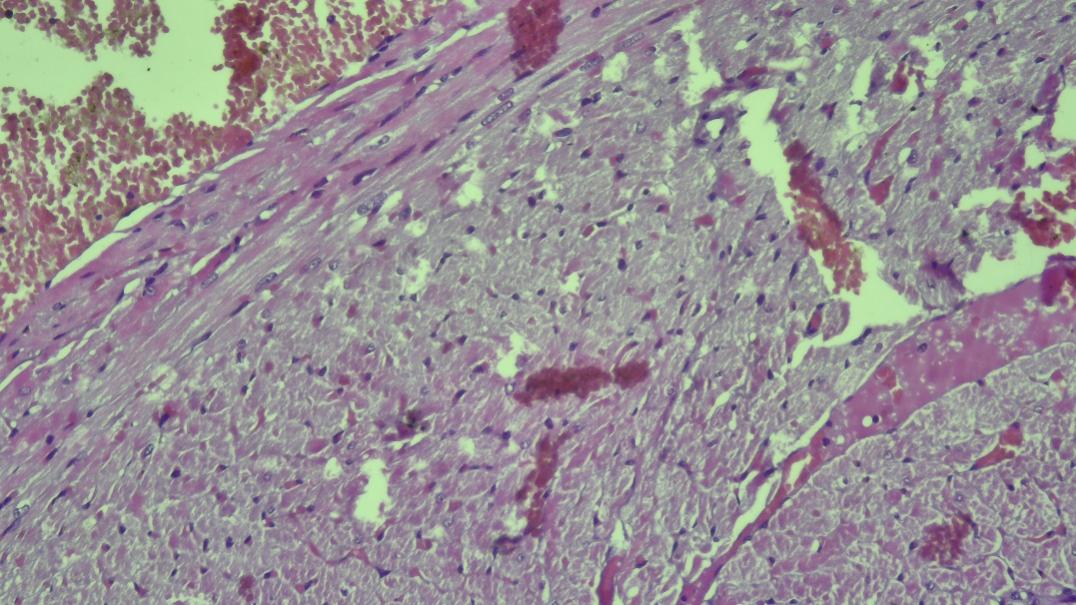

On the third day of life, the histological structure of the myocardium of rat pups born to mothers with metabolic syndrome did not differ from that of the control group. Cardiomyocytes formed elongated muscle fibers, with oval nuclei located in their central part and clearly expressed myofibrils.During the period of breastfeeding, on the seventh day of the experiment, the results of morphometric analysis showed a decrease in the thickness of the walls of all sections of the heart compared to the control group. In the small blood vessels of the heart, there were hemorrhages of a stasis and diapedesis nature, which were accompanied by perivascular edema, disorganization of the stroma and swelling of connective tissue elements. Also, dilated and full-blooded blood vessels were detected in the subepicardial zone. Initial edema was observed in the myocardial stroma.On the fourteenth day of the experiment, an increase in edema was observed in the myocardial stroma, mainly in the perivenular and pericapillary areas. Collagen fibers swelled, and superficial disorganization of the connective tissue structure began to develop. Blood vessels appeared rounded due to swelling of endothelial cells. In cardiomyocytes, cytoplasmic vacuoles, i.e., accumulation of clear fluid in the cytoplasm, were observed, and signs of hydropic dystrophy were noted. These swelling processes were focal, and dystrophic and unchanged cardiomyocytes were observed together. Lymphohistiocytic infiltration was also noted.On the 21st day of the experiment, changes in blood vessels in the myocardial tissue remained. Perivascular hemorrhages in the form of blood accumulation, stasis, and diapedesis were detected in the veins. The accumulation of fluid in the muscle tissue led to the friction of muscle fibers against each other. Small infiltrates consisting of lymphocytes, histiocytes, and fibroblasts were also detected in the myocardium. Signs of mucoid and fibrinoid staining were noted in the myocardial stroma. Protein hydropic dystrophy developed in cardiomyocytes, swellings and foci of plasmolysis were observed inside the cells. Plasmolysis foci appear under a microscope in a similar way to optical cavities. Cases of vacuolization are detected in the cytoplasm of cardiomyocytes. Thickened and swollen collagen fibers are noted in the endocardium. Initial changes of atherosclerosis were detected in the wall of arterioles. No changes were detected in the endothelial layer of the arterial wall, foam cells were detected in the subendothelial layer.On the 21st day of the experiment, a slight thickening of the basement membrane of the subendothelial layer, edema in the interstitial tissue and foci of fibrous structures, surrounded by a large amount of infiltration of macrophages and lymphocytes, was detected. Atrophic and focal hypertrophic changes were detected in the sparsely located muscle cells of the mediastinum.On the 28th day of the experiment, interstitial edema in the myocardium further increased and spread widely throughout the heart muscle tissue (Fig. 4).  | Figure 4. On the 28th day of the experiment, interstitial edema spread in the subepicardial branch of the myocardium |

This swelling process occurs with a significant expansion and spread of collagen fibers. The myocardium itself swells, and a disruption (disorganization) of the structure of the surrounding connective tissue fibers is observed. Dystrophic changes are diffuse (i.e., widespread) in nature, manifested by the absorption of the cytoplasm and the increase in intracellular swelling. The spread of muscle fibers and focal edema elements are detected. These changes are especially pronounced in the subendocardial part of the myocardium. During this period of the experiment, changes were also observed in the arterial blood vessels in the ventricular wall.